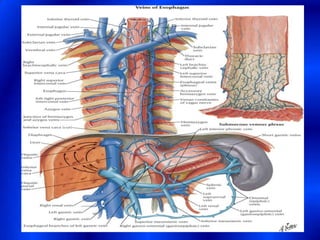

This document provides information about a barium swallow procedure. It begins with an introduction and overview of the embryology and anatomy of the pharynx and esophagus. It then describes the procedure itself, including preparation, technique, views obtained, and indications. Specific conditions that may be examined include pharyngeal and esophageal webs, foreign body impaction, scleroderma, dysphagia, mediastinal masses, and carcinoma. Diagrams are provided to illustrate normal anatomy and various pathological findings.